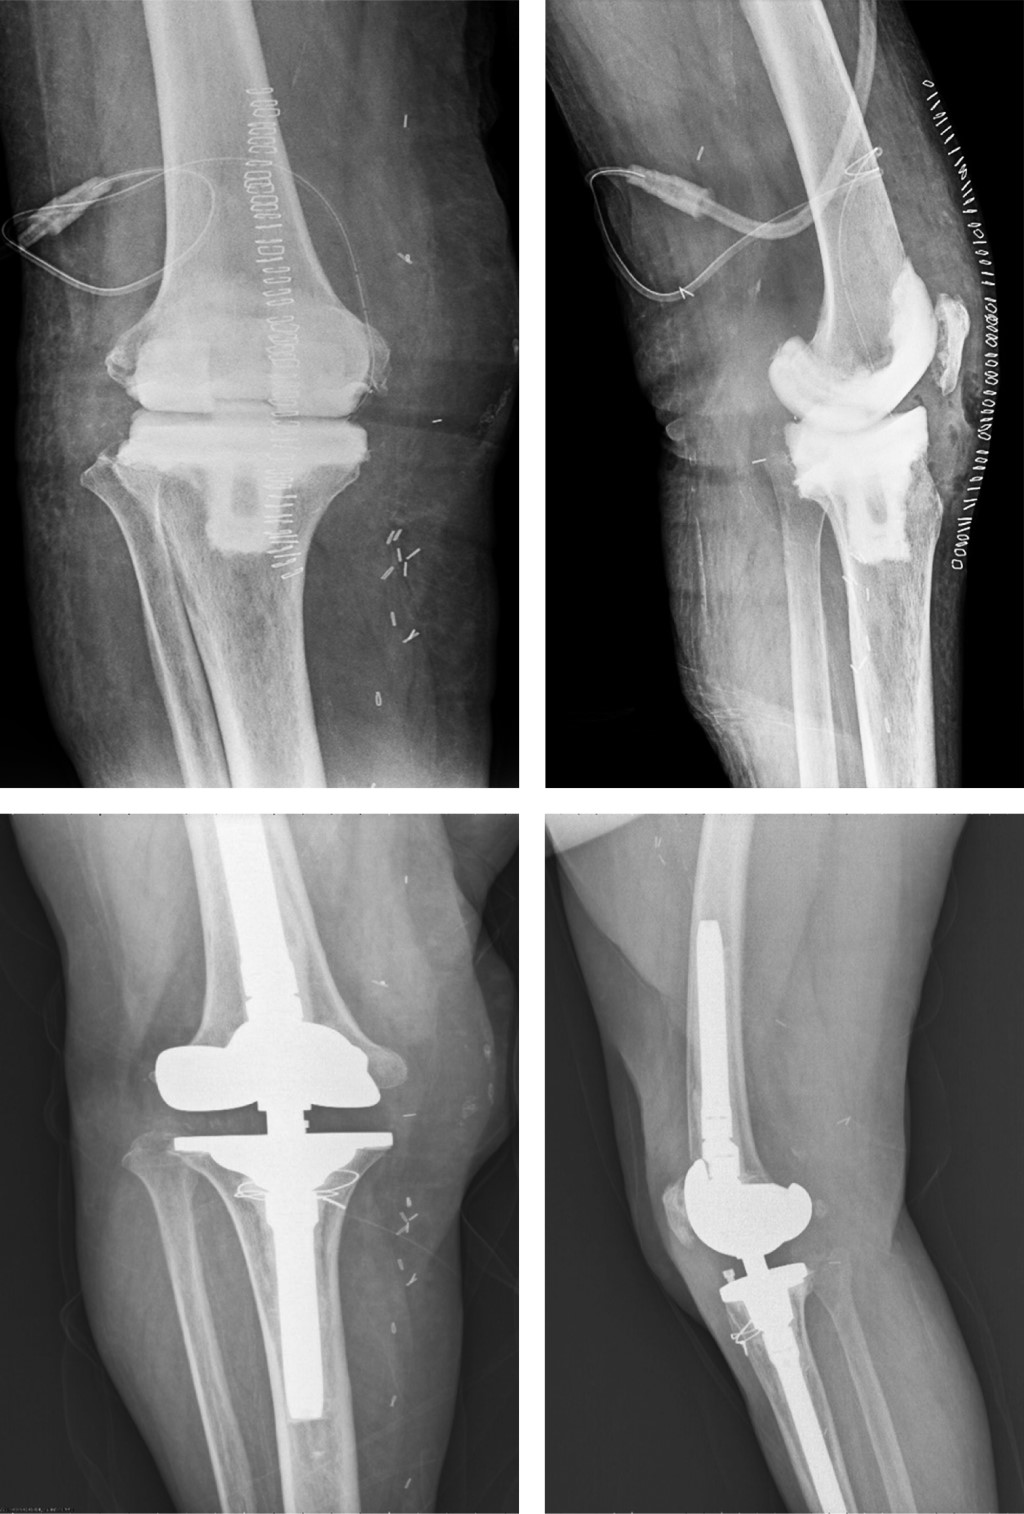

Figure 2